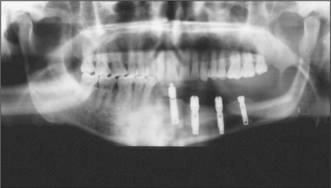

Microvascular tissue transfer is currently favoured for immediate mandibular reconstruction. The radial forearm flap with soft tissue and a section of the radius, the compound groin flap based on the deep circumflex iliac vessels and free fibula flaps have all been advocated. A problem with the radial flap is that the harvested bone, although restoring mandibular continuity, often does not provide sufficient bulk for prosthetic reconstruction. Both the fibula and the groin flap provide sufficient bone stock to allow the insertion of osseointegrated implants (Fig. 10.13) and thus full dental rehabilitation postoperatively.

image

Fig. 10.13 Implants within a reconstructed mandible, following resection for carcinoma.